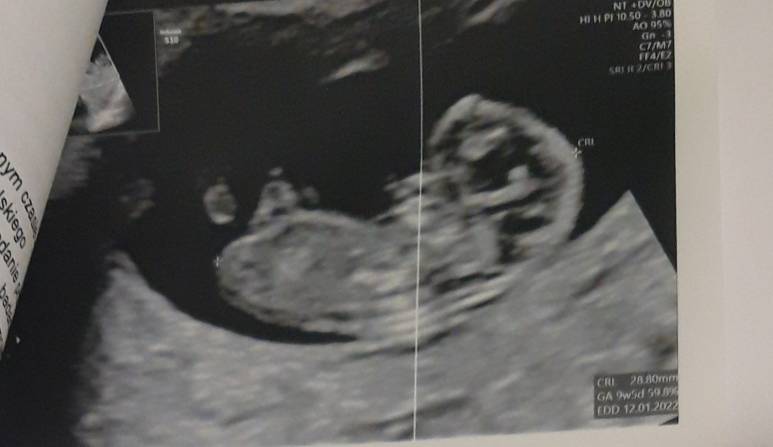

Gratulacje <3 piękne maleństwo, ja swoje ostatni raz widziałam w 8+4 tc, za tydzień mam prenatalne i już wytrzymać nie mogę, odstęp 4 tygodni to wieczność!Wszystko dobrzeprenatalne 6.07 , widziałam jak rusza rączkami i nóżkami ♡♡♡ cudownie ufffZobacz załącznik 1282762Zobacz załącznik 1282763

Wszystko dobrzeprenatalne 6.07 , widziałam jak rusza rączkami i nóżkami ♡♡♡ cudownie ufffZobacz załącznik 1282762Zobacz załącznik 1282763

Piękny,malutki Człowieczek